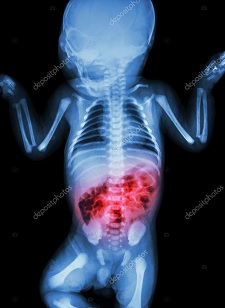

Enterocolitis: La enterocolitis o coloenteritis es una inflamación del tracto digestivo, implicando enteritis del intestino delgado y colitis del colon. Pueda ser causada por varias infecciones, con bacterias, virus, hongos, parásitos, u otras causas.

- Distensión abdominal.

- Sangre en las heces.

- Diarrea.